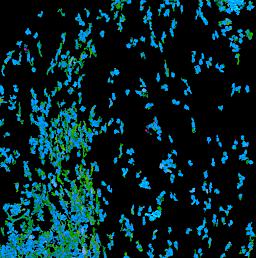

Pancreatic ductal adenocarcinoma is a lethal disease with limited treatment options and poor survival. We studied 83 spatial samples from 31 patients (11 treatment-naïve and 20 treated) using single-cell/nucleus RNA sequencing, bulk-proteogenomics, spatial transcriptomics and cellular imaging. Subpopulations of tumor cells exhibited signatures of proliferation, KRAS signaling, cell stress and epithelial-to-mesenchymal transition. Mapping mutations and copy number events distinguished tumor populations from normal and transitional cells, including acinar-to-ductal metaplasia and pancreatic intraepithelial neoplasia. Pathology-assisted deconvolution of spatial transcriptomic data identified tumor and transitional subpopulations with distinct histological features. We showed coordinated expression of TIGIT in exhausted and regulatory T cells and Nectin in tumor cells. Chemo-resistant samples contain a threefold enrichment of inflammatory cancer-associated fibroblasts that upregulate metallothioneins. Our study reveals a deeper understanding of the intricate substructure of pancreatic ductal adenocarcinoma tumors that could help improve therapy for patients with this disease.